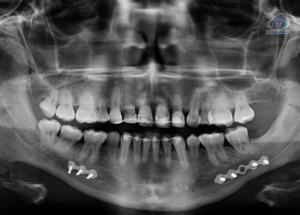

Caso 300 – IDM – HIPERPLASIA DE APÓFISIS CORONOIDES DE LADO DERECHO – IDM

Paciente femenino de 16 años acude al Instituto de Diagnóstico Maxilofacial (sede Miraflores) para evaluación quirúrgica. Radiografia Panorámica A la evaluación de la radiografía panorámica